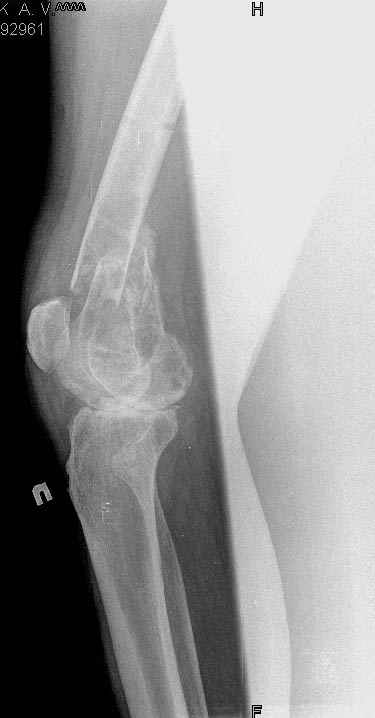

Коллеги!Окажите, пожалуйста, консультативную помощь.Мужчина, 41 год, 15 лет состоит на учете по поводу ревматоидного полиартрита, гормонзависимый (преднизолон получает нерегулярно). В процесс вовлечены крупные и мелкие суставы. 01.01.06 - без травмы наступил патологический перелом на границе н/3-с/3 бедра (перелом на фоне кистозных изменений?) Биопсия из зоны перелома - <реактивные изменения в очаге перелома>, без признаков опухоли. На рентгенограммах, помимо перелома, кистозные изменения на мыщелках б/берцовой кости и мыщелке бедра с другой стороны. До травмы со стороный коленных суставов был болевой синдром, функция практически в полном объеме. Какие будут предложения по тактика лечения перелома и кист на противоположом бедре? Заранее благодарю! С уважением, А.В.Владзимирский Донецкий НИИ травматологии и ортопедии Донецк, Украина

Штифтование с блокированием, у себя бы сделали антгеградно, можно и ретроградно. Чтобы конструкция не вырезалась, лучше бы сделать какую-то augmentation - в каналы винтов ввести цемент, если есть возможность, то не метилметакрилатный, а типа Norian SRS или MIIG.